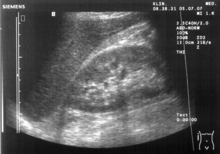

Abdominal ultrasonography (also called abdominal ultrasound imaging or abdominal sonography) is a form of medical ultrasonography (medical application of ultrasound technology) to visualise abdominal anatomical structures. It uses transmission and reflection of ultrasound waves to visualise internal organs through the abdominal wall (with the help of gel which helps transmission of the sound waves). For this reason, the procedure is also called a transabdominal ultrasound, in contrast with endoscopic ultrasound, the latter combining ultrasound with endoscopy through visualize internal structures from within hollow organs.

Ultrasound imaging is useful for detecting stones, for example kidney stones or gallstones, because they create a clearly visible ultrasound shadow behind the stone.